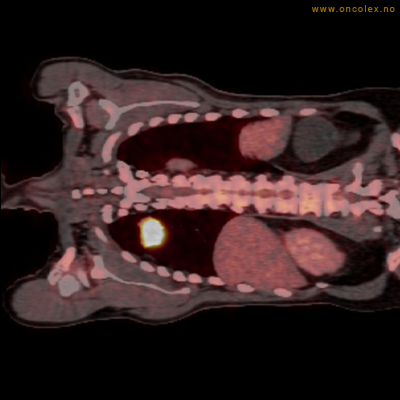

Eksempler på funn

Vev som tar opp mer radioaktivt stoff, synes som hvite områder som lyser opp mer i forhold til annet vev som tar opp mindre sukker.